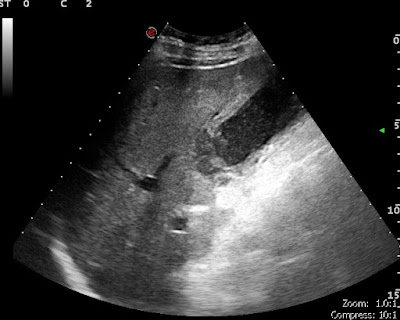

a beteg típusos jobb bordaív alatti panaszokkal érkezettzárókő az epehólyag nyakában körkörös, réteges fali megvastagodással

L.Z. találata Megvastagodott, réteges szerkezetű epehólyagfal. Sűrű epetartalom, kövek. Következményes peritonitisre utaló híg tartalommal telt, peristalticát nem mutató vékonybélkacsok látszódtak a kismedencében5x190792